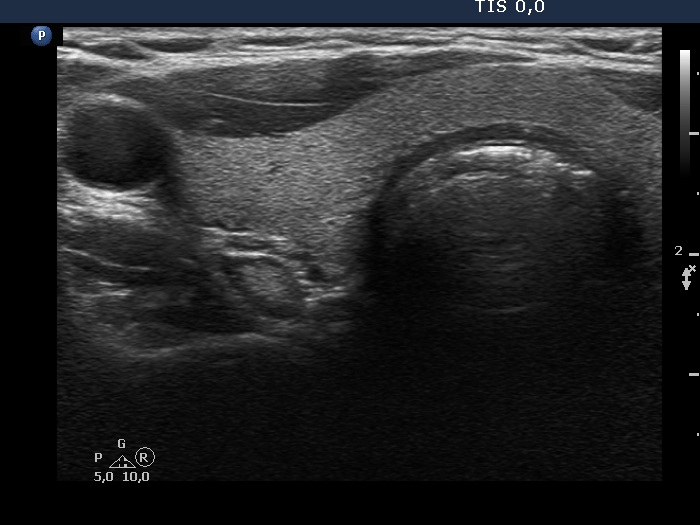

Ultrasonography. The thyroid was echonormal. There was a dominantly hypoechoic nodule in the left lobe. The nodule had both microcalcifications and macrocalcification and was avascular.